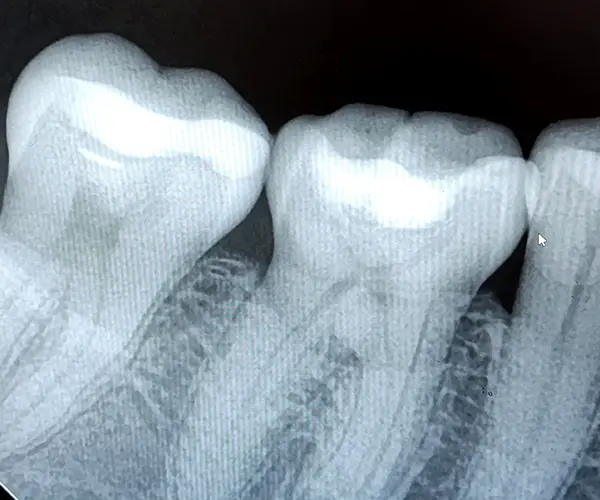

Контроль: рентгеновские снимки